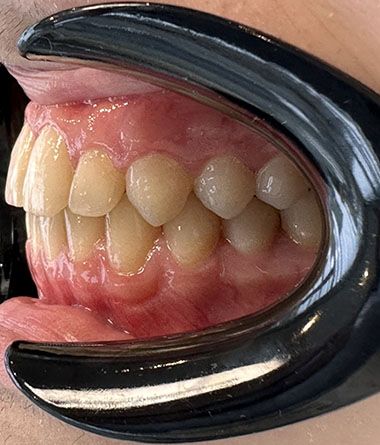

Glenn T. broke 2 teeth as a result of an accident in his childhood. These teeth were filled and the fillings were aged. Glenn was unhappy because of the gaps between his teeth. He also did not like the angle of his front two teeth. He wanted to have his teeth done before he started university. He decided to have invisalign in Turkey with his family.